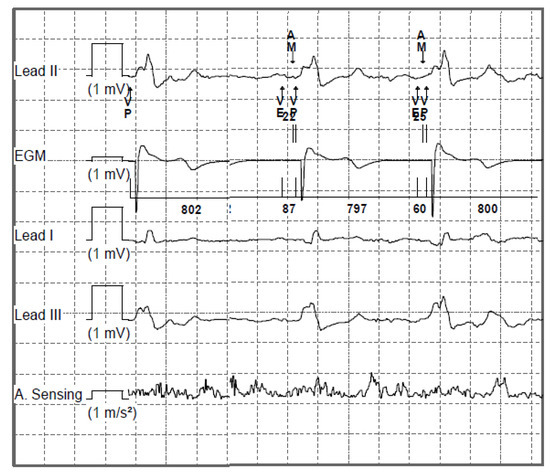

- Chinitz, L.; Ritter, P.; Khelae, S.K.; Iacopino, S.; Garweg, C.; Grazia-Bongiorni, M.; Neuzil, P.; Johansen, J.B.; Mont, L.; Gonzalez, E.; et al. Accelerometer-based atrioventricular synchronous pacing with a ventricular leadless pacemaker: Results from the Micra atrioventricular feasibility studies. Heart Rhythm. 2018, 15, 1363–1371. [Google Scholar] [CrossRef] [PubMed]

- El-Chami, M.F.; Bhatia, N.K.; Merchant, F.M. Atrio-ventricular synchronous pacing with a single chamber leadless pacemaker: Programming and trouble shooting for common clinical scenarios. J. Cardiovasc. Electrophysiol. 2021, 32, 533–539. [Google Scholar] [CrossRef]